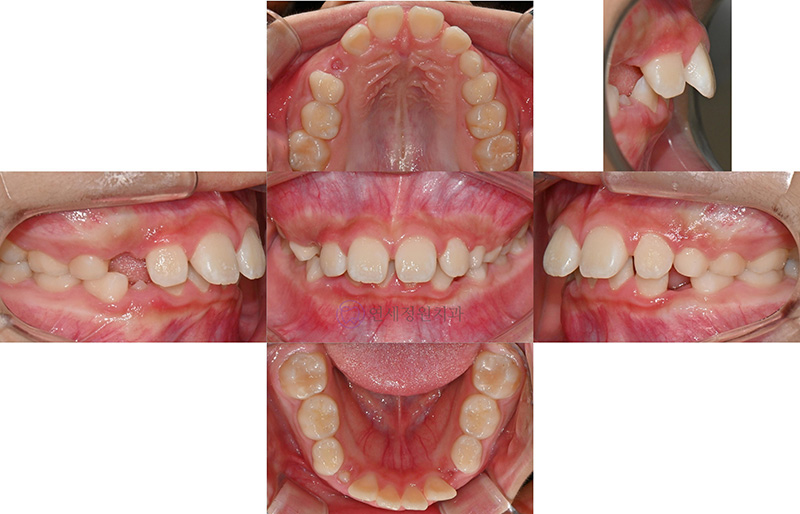

위 케이스는 아래턱의 성장이 부족하여 위 치아는 돌출되어 있으며 힘을 주어야 입술을 다물 수 있고, 근육에 힘이 들어가다보니 턱 밑에 호두 주름이 생겼지요. 게다가 아래 입술에는 그림자가 생기게 되었답니다. 위 앞니가 돌출되어 있고 깊게 물리다보니 아래 치아는 잘 보이지 않게 되구요.

이런 경우 아래턱의 위치를 앞으로 내밀어주어 과개교합을 개선하기 위한 Activator 장치를 착용합니다. 수직적인 성장도 함께 조절해 주기 위하여 헤드기어라는 장치도 함께 착용합니다.